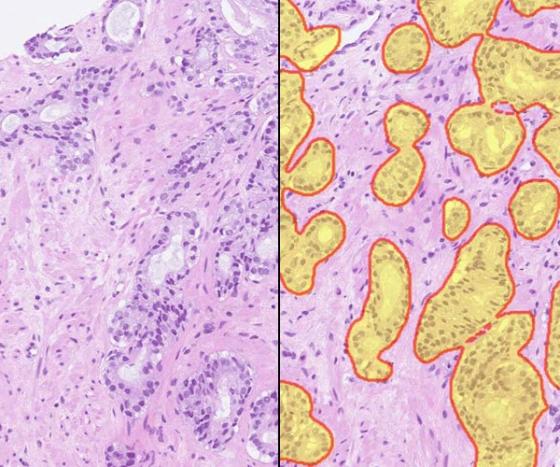

Prostate H&E digital slide (left) with Prostate AI markup (right) identifying Gleason pattern 3 (yellow). Tumor boundary highlighted with red lines.

Developed by Indica Labs, the Prostate AI solution leverages deep learning technology to standardize the scoring of H&E stained prostate core needle biopsy samples. The algorithm reports quantitative results and markup images, including tumor localization, size and Gleason scores.